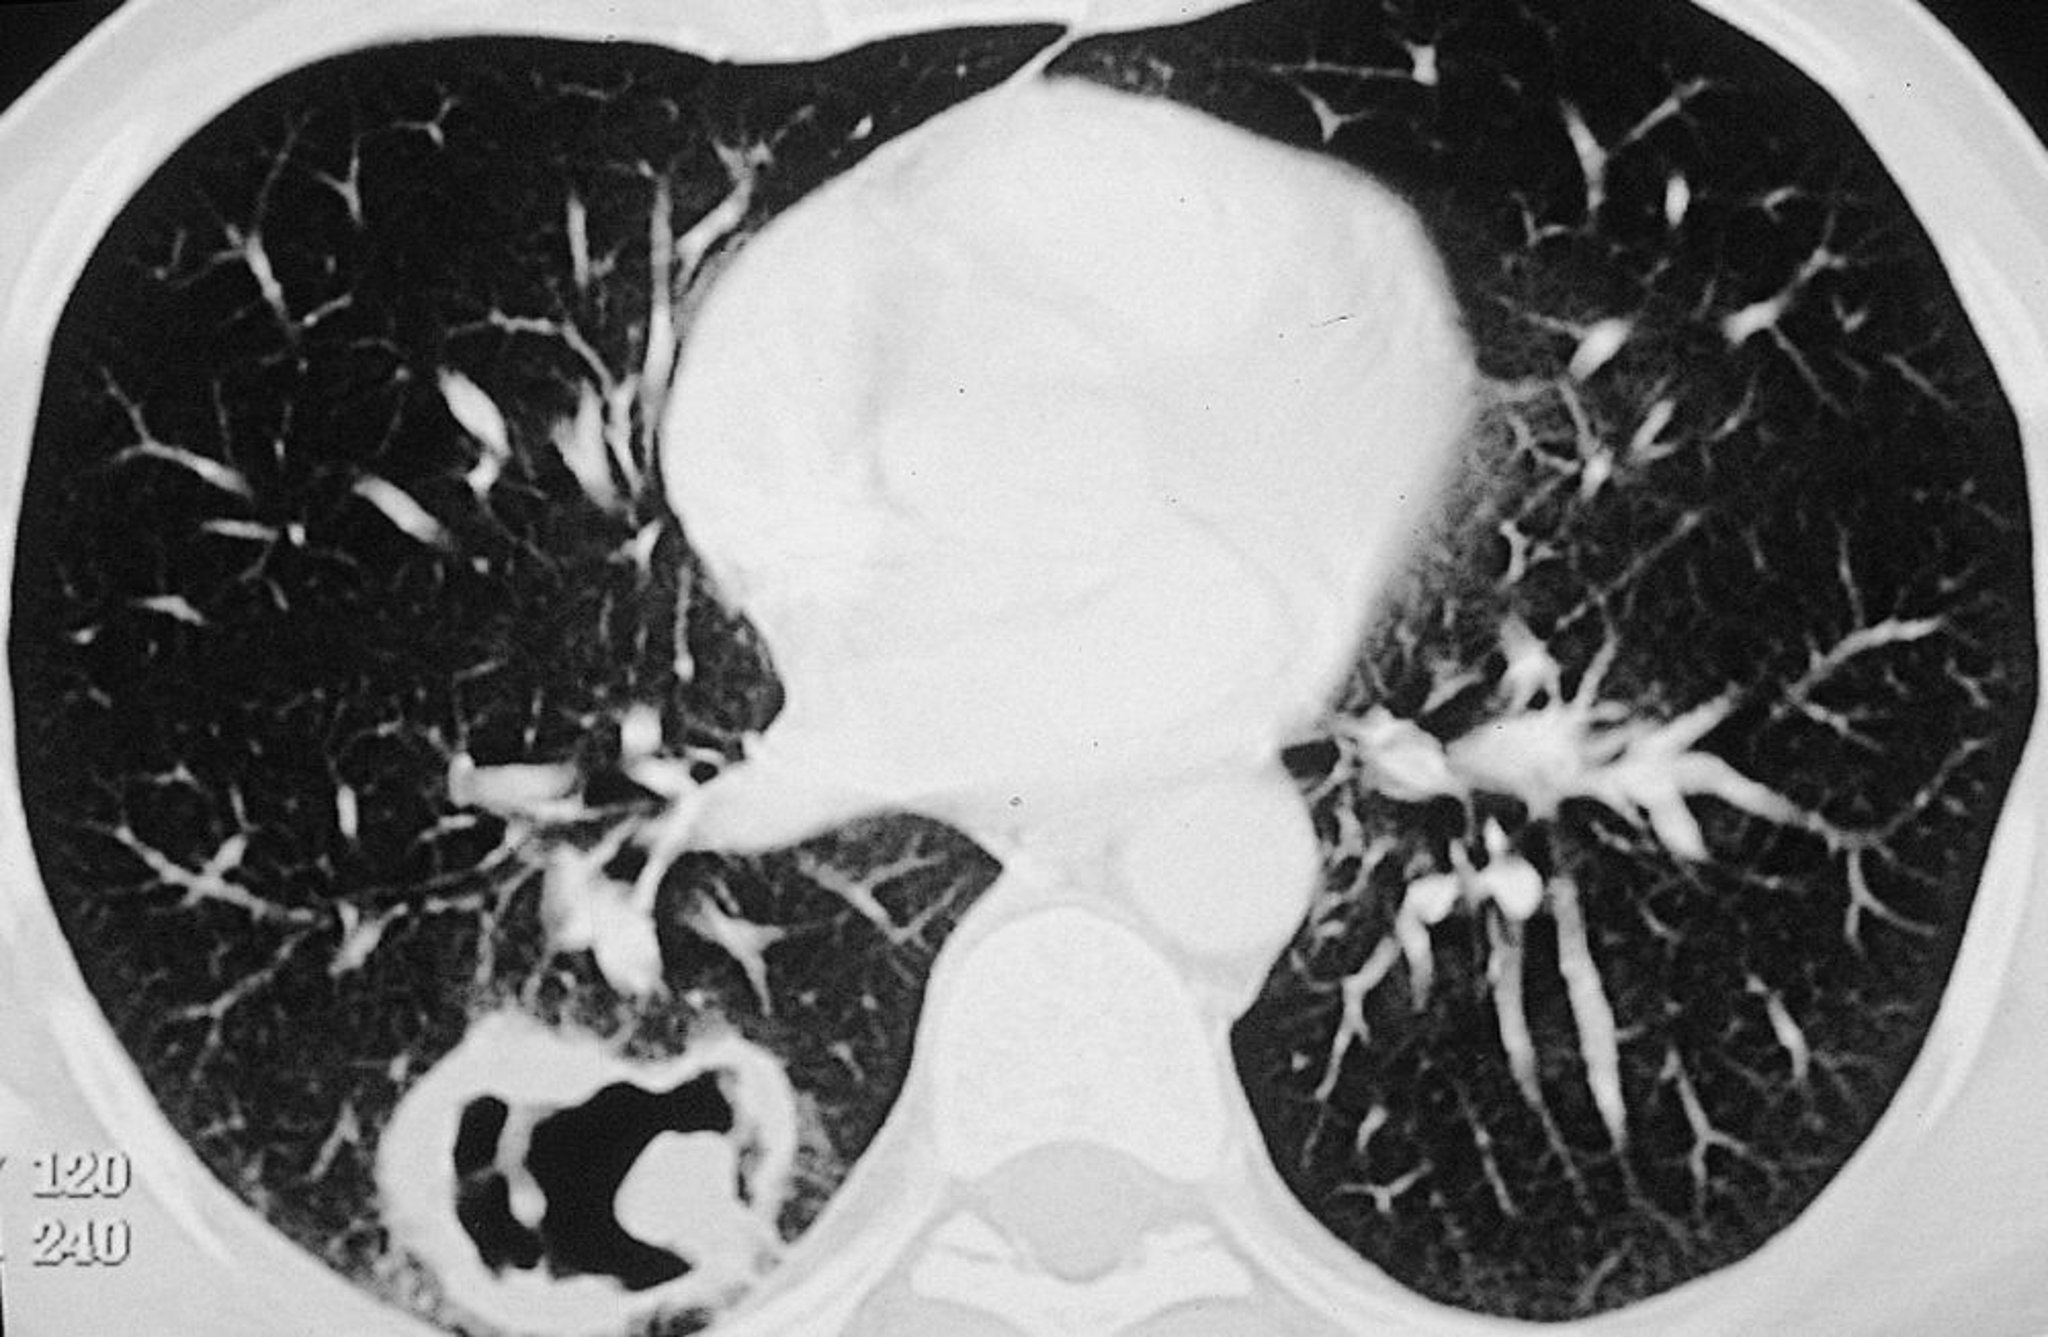

Granulomatose avec polyangéïte (lésion pulmonaire)

Grande lésion cavitaire du poumon droit chez un patient atteint de granulomatose avec polyangéïte.